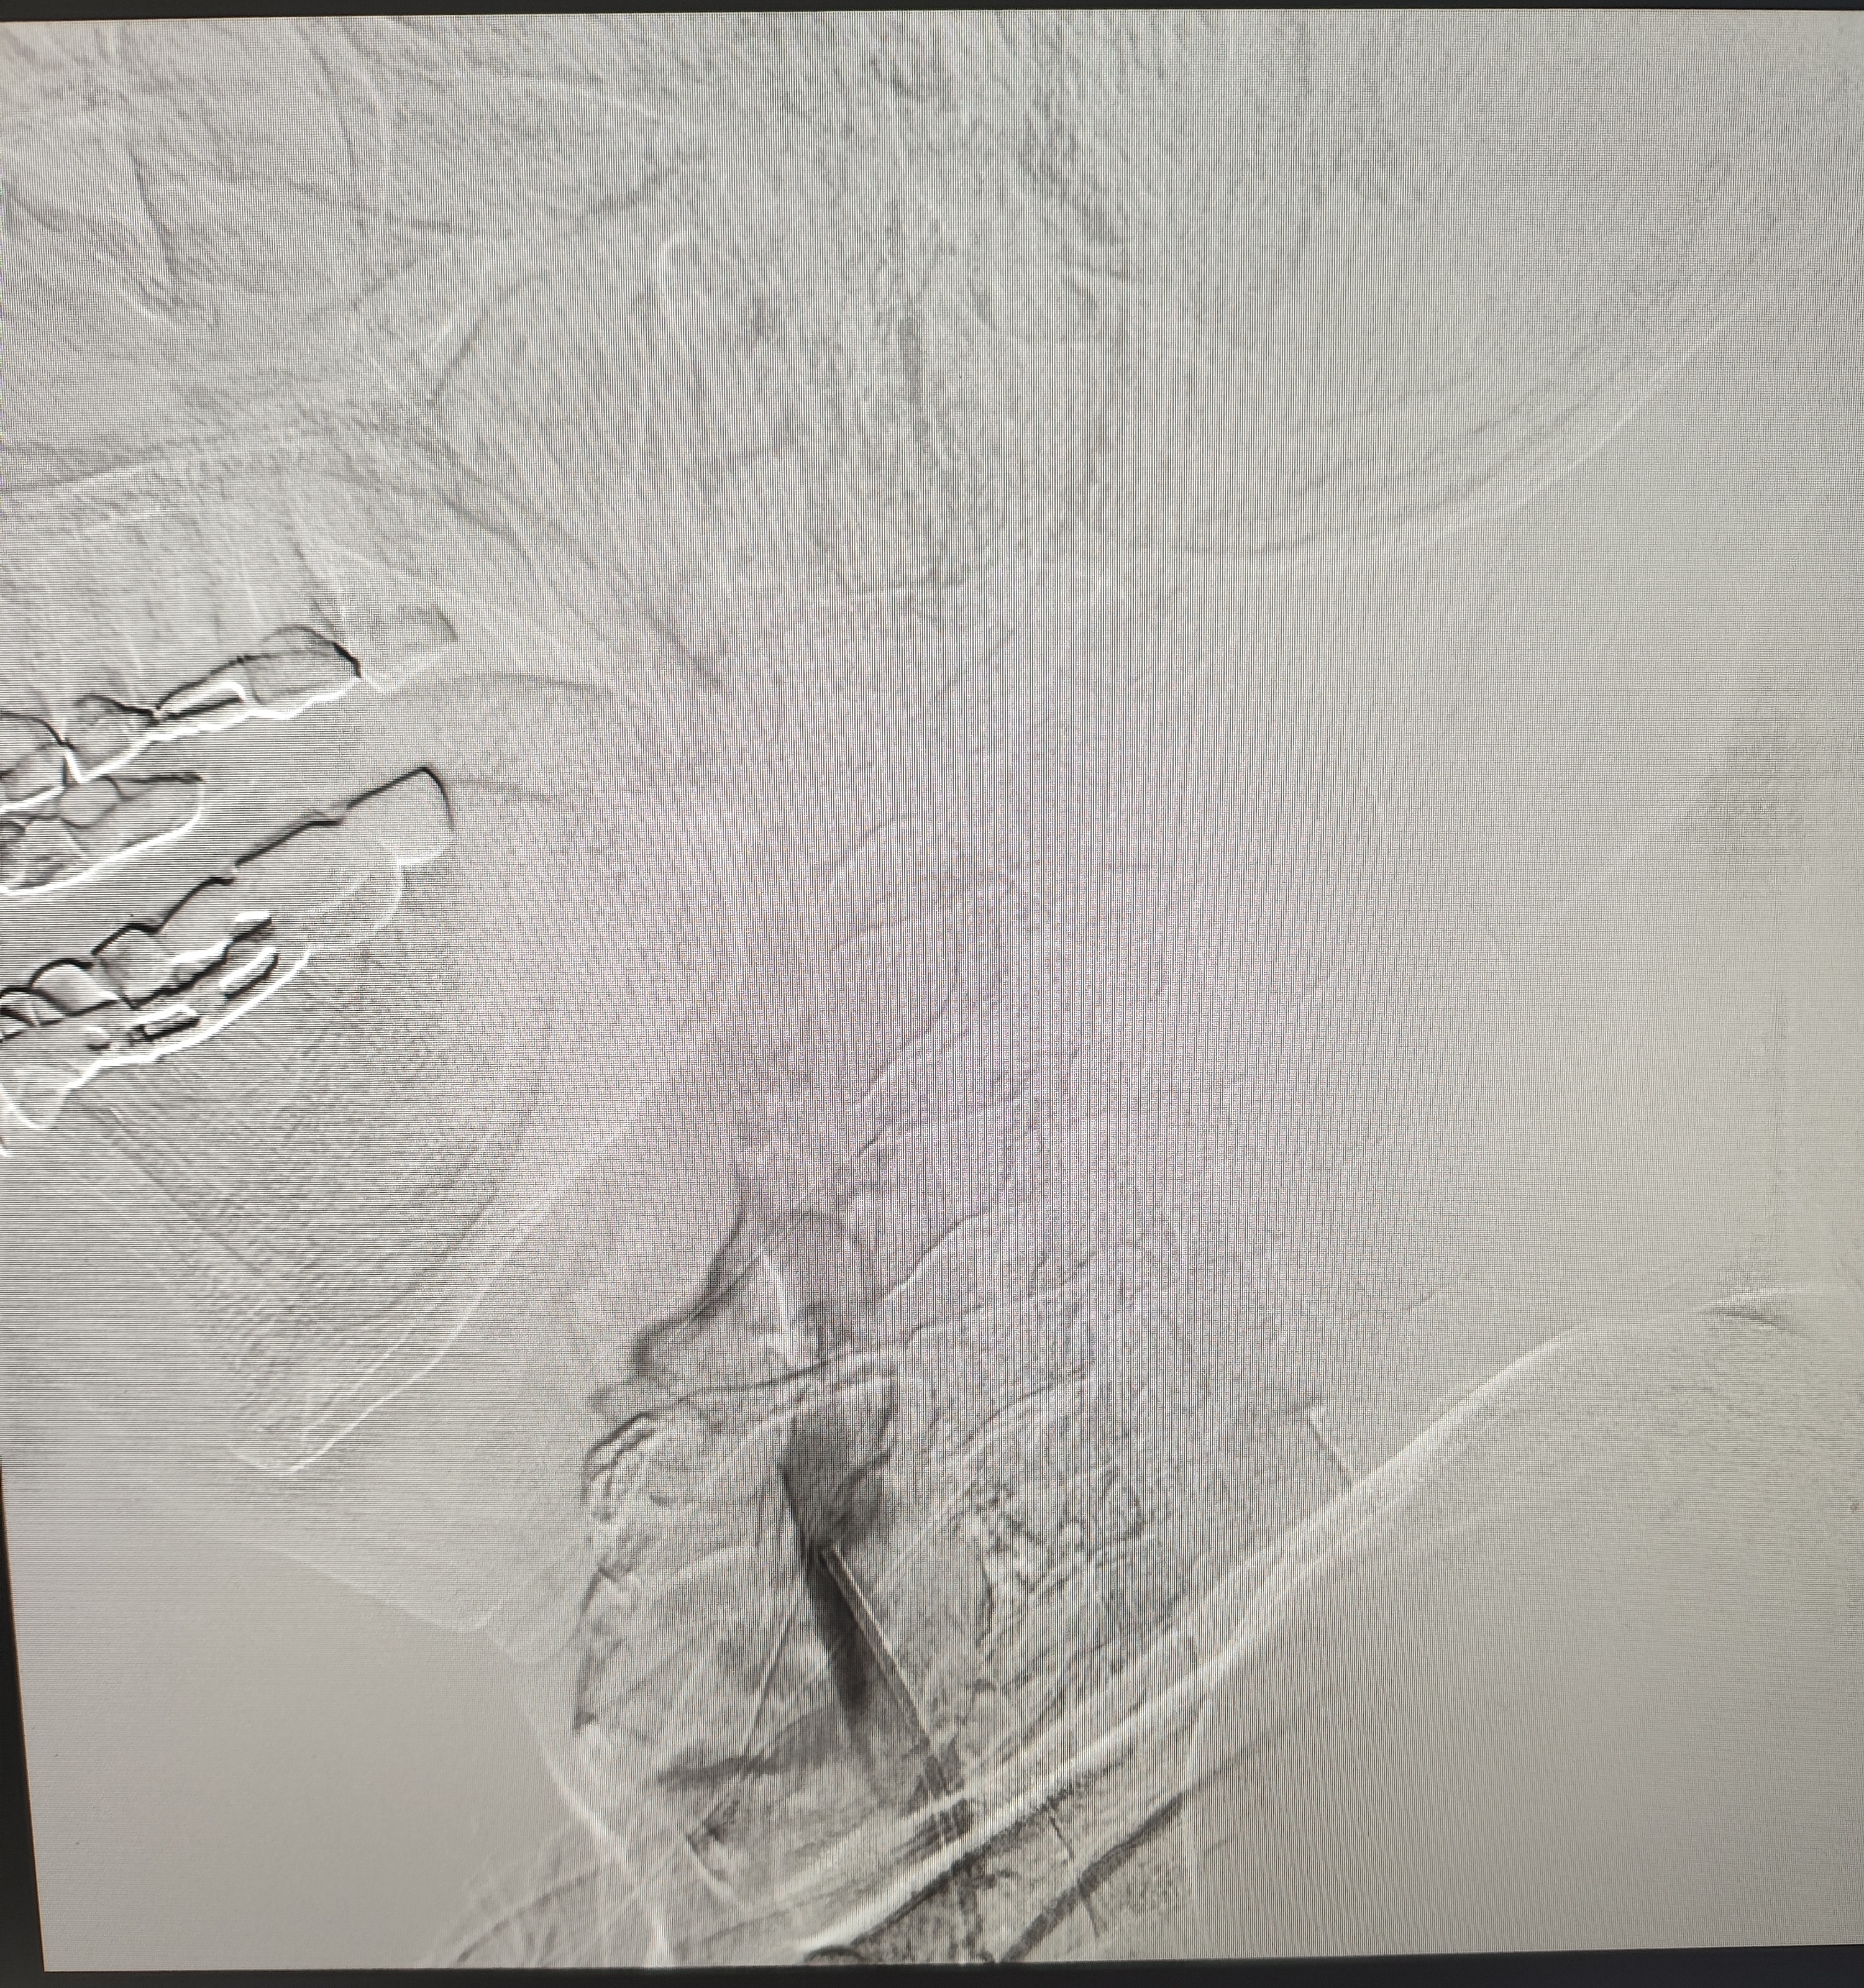

颈总巨大斑块急性闭塞的血管内治疗(双颈动脉支架桥接+支架释放后掉斑块,抽吸取栓)

84岁男性,既往右侧颈动脉狭窄病史8个月,多次脑梗未治疗,本次突发左侧肢体无力来诊,发病30小时后转入我院。

症状进行性加重,意识逐渐模糊,烦躁,左上肢肌力1级,左下肢肌力2级,当地考虑开通难度大,转入我院。

急诊上台。